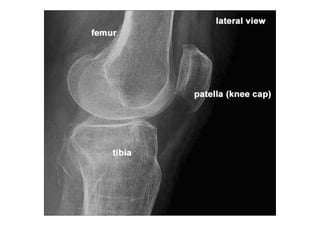

RADIOLOGIA DO

TRAUMA DO ESQUELETO

Referência: http://www.accessexcellence.org/RC/VL/